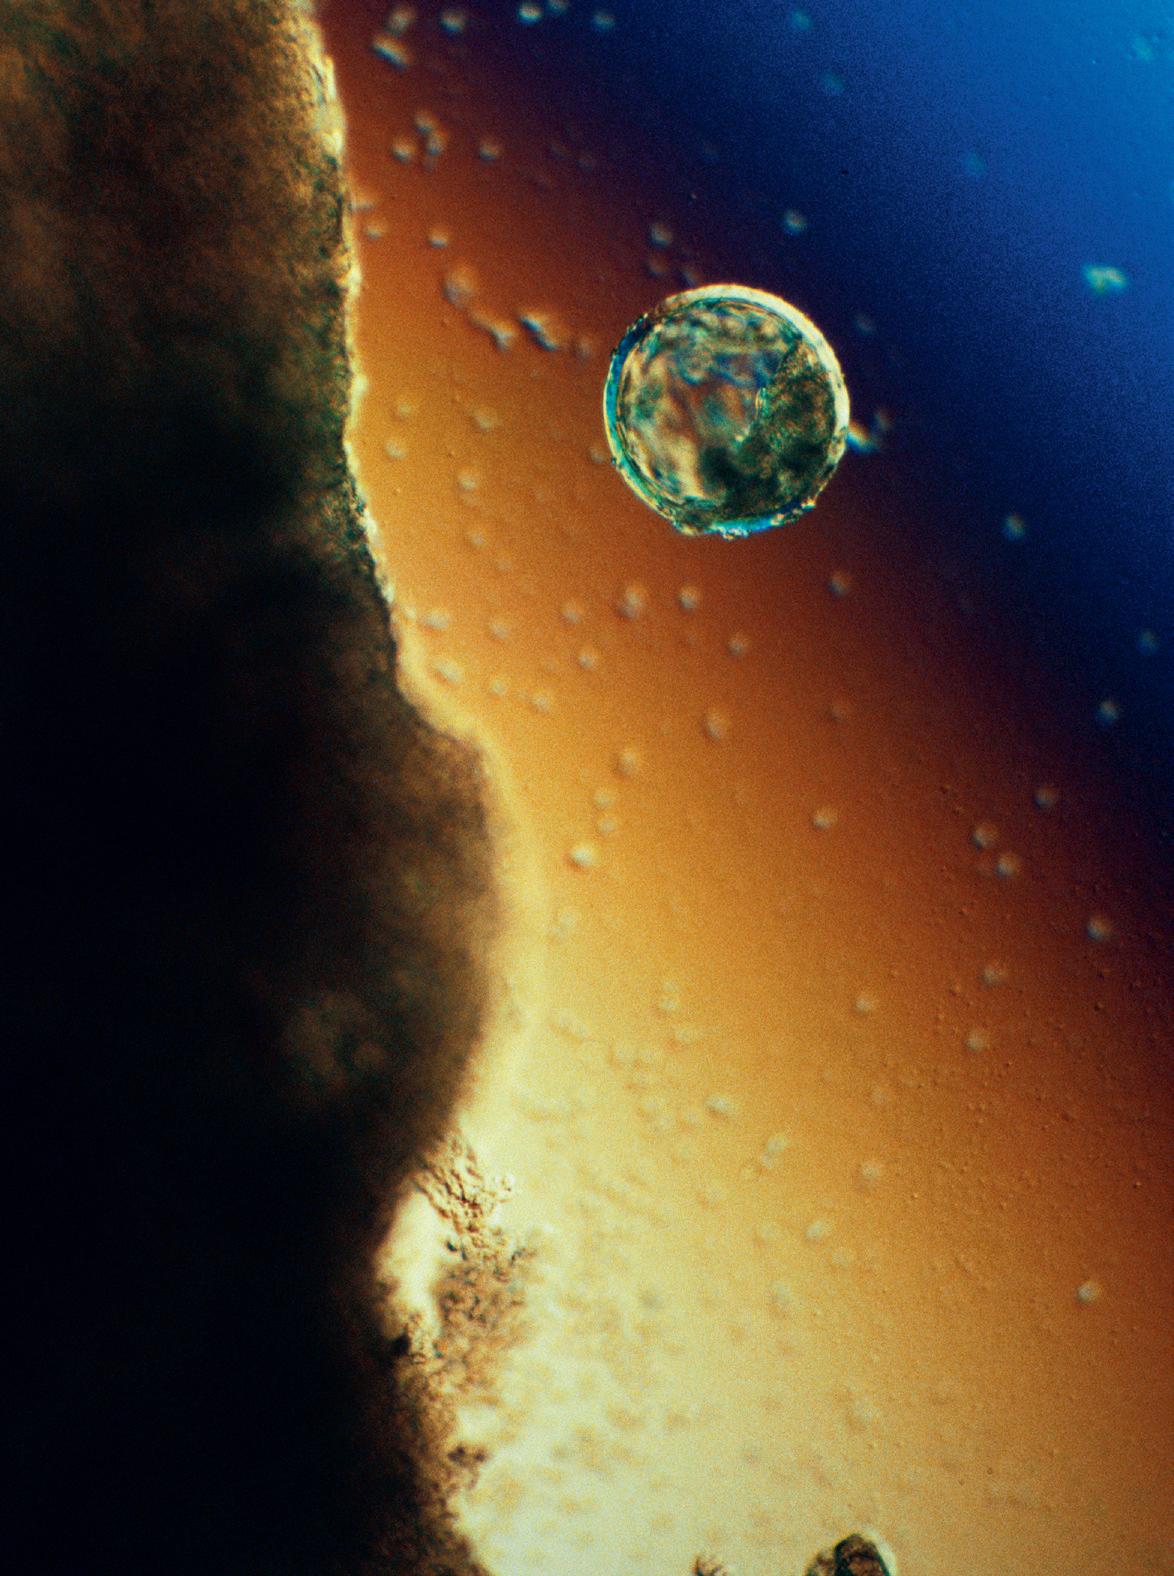

< Blastocysten på väg att landa i livmodern, men först måste den göra sig fri från det omgivande äggskalet.

Under kläckningen tumlar blastocysten runt inne i livmodern. Av och till stöter den emot den mjuka livmoderslemhinnan. Äggskalet brister och den ömtåliga cellmassan kommer ut.

(nästa uppslag) Efter kläckningen vidgar sig embryot snabbt och skulle inte längre få plats i skalet, som inte längre behövs. Sakta sjunker den fredliga inkräktaren in i livmoderns slemhinna.

När blastocysten väl tagit sig igenom äggledaren och kommit ut i livmodern finns det gott om utrymme. Livmodern är väl förberedd. Efter ägglossningen har livmoderslemhinnan haft drygt sex dagar på sig för att bli riktigt fint utvecklad, det vill säga just den tid det tar för ägget att komma ut ur äggblåsan, befruktas i äggledaren, färdas mot livmodern och landa på rätt ställe. Embryot ”väljer” noga den plats i livmodern där det ska slå sig ner. Man tror att det skickar ut kemiska signaler till sin omgivning och att omgivningen svarar på invitationen genom att erbjuda en bra miljö för utveckling och tillväxt. Strax före landningen i slemhinnan drar sig blastocysten samman och sväller upp igen minst tre fyra gånger. Embryot och moderkakan gör sig av med sitt omgivande skal – ett slags kläckning sker. Om embryot är friskt och utvecklingsbart lyckas kläckningen och det genomskinliga, tomma skalet seglar iväg och löses upp.

Skalets utsida har varit relativt jämn och hård, men ytan hos den nykläckta cellmassan är mer böljande i sin form och dessutom mycket klibbigare – det är som om hela embryot har doppats i sockerlag. Sockermolekylernas utskott sträcker sig mot livmoderslemhinnans yta, som i sin tur har likartade sockermolekyler där utskotten passar in.

Den allra första kontakten mellan embryot och livmoderns slemhinna är en kritisk process där många faktorer måste samverka på bästa sätt för att allt ska fungera. Det är embryocellerna och inte moderkakscellerna som tar initiativet till vidhäftningen i livmoderns slemhinna, den så kallade implantationen. Oftast fäster embryot i livmoderns övre del.